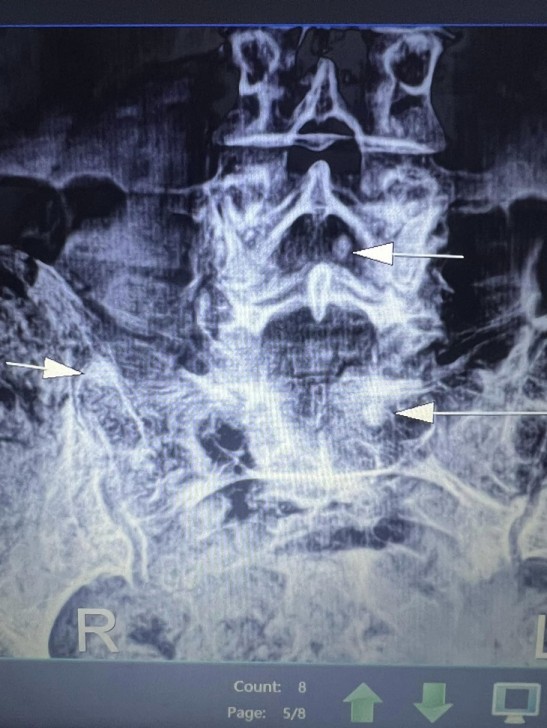

AFN.az xəbər verir ki, tanınmış həkim Aydın Əliyev bu sahədə vəziyyətin getdikcə ağırlaşdığını bildirib. O, xəstələrdən birinin müayinə nəticələrini paylaşaraq bunları yazıb: “Onkoloji xəstəliklərin müayinə və müalicəsinin hələ də icbari tibbi sığorta tərəfindən qarşılanmamasının daha bir qurbanı. Sağ qamış sümüyündəki törəmənin maddi imkansızlıq səbəbindən vaxtında və sistemli müalicə və ya əməliyyat edilməməsi səbəbindən fəqərələrə, qabırğalara, kürək, çanaq sümüklərinə, ağciyərə çoxsaylı metastazları. Demək olar ki, adam həyatını itirib”.